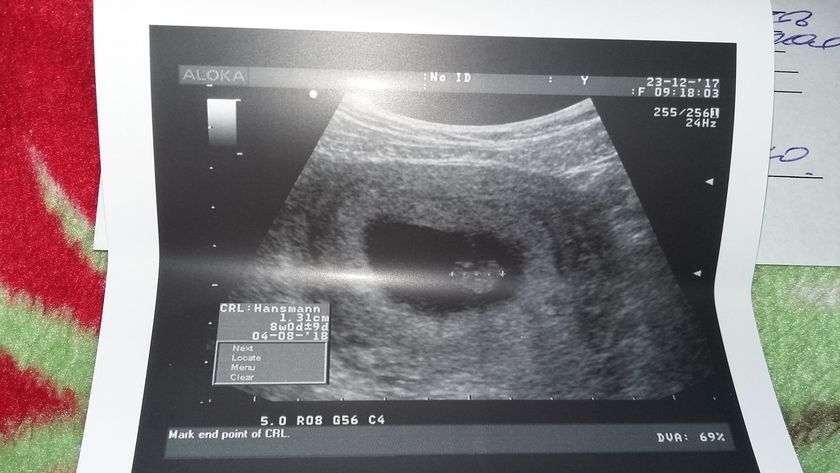

Мои надежды и молитвы все таки сбылись. У второго малыша забилось сердечко??? мои крошечки как же я рада что вы оба живы и здоровы. На данном этапе все хорошо. Один малыш соответствует 7 нед второй 8. Сердечко у одного 163/165 у второго. Конечно узистка мне сказала что это очень сложная беременность. И что гарантий мне никто не даст что все будет хорошо с детками. Но я верю в лучшее. Фото крошек? нафоткала их из разных углов? двоих не смогла поймать

Здорово???хорошо что все хорошо??? а мы 11 и 13 мм?